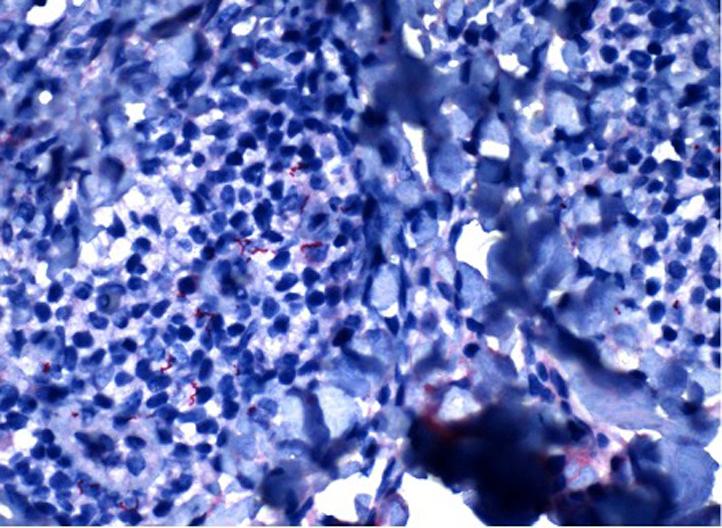

A case of secondary syphilis masquerading as cutaneous lymphoma.

JAAD Case Rep. 2021 Jun 9;14:17-20. doi: 10.1016/j.jdcr.2021.05.036. eCollection 2021 Aug.